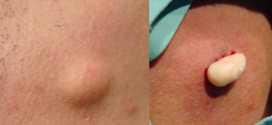

Leer MásQUISTES SEBÁCEOS

Los quistes sebáceos. Tumor, quiste, etc; normalmente es benigno constituido por una masa circunscrita de tejido adiposo ó constituidos por la proliferación de tejido celular subcutáneo. Es un tumor, quiste, absceso, etc; benigno compuesto de tejido adiposo, a veces encapsulado que se manifiestan como masas redondas bien definidas con una pared visible y homogénea. Tiene un crecimiento lento de masa …